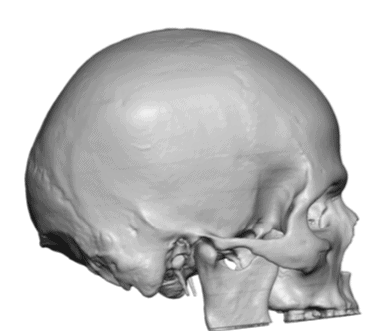

Desire for increased crown of head augmentation.

Crown of skull augmentation using a custom skull implant.

Desire for increased crown of head augmentation.

Crown of skull augmentation using a custom skull implant.